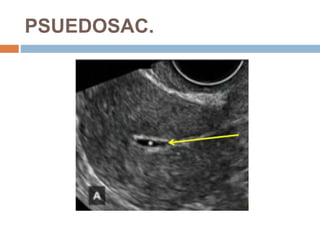

PSUEDOSAC.